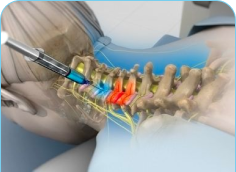

Radiofrequency Ablation may be used in cervical, thoracic, and lumbar spine. It can also be used in the sacroiliac joint and peripheral nerves, where the procedure is employed to reduce pain from the arthritic joints. Radiofrequency Ablation is a technique that employs heat to disable the pain-transmitting nerves in the spine.

The procedure is very safe and is only used on sensory nerves that transmit pain impulses. There is no risk of paralysis or weakness from this procedure. Radiofrequency Ablation uses heat to disable the pain-transmitting nerves in the spine. The process is analogous to microwave ovens that use microwave energy to heat food. Radiofrequency Energy is transmitted to the tip of a needle where it is converted to heat, which is applied directly to the nerve fibers. Once the nerves undergo this heat treatment, they slowly stop transmitting pain.